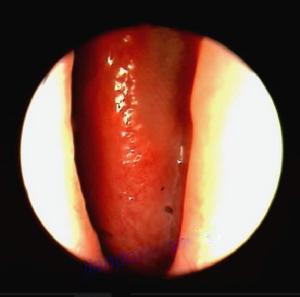

鼻窦炎案例图

在鼻内镜的直视下手术,保留鼻腔鼻窦的生理功能,扫净病灶,改善和重建鼻及鼻窦的通气引流,恢复粘膜(纤毛及腺体)的形态和生理功能,达到治愈 目的。手术时,先以CT片和鼻内窥镜进行精确定位左右4对:称额窦、上颌窦、筛窦和蝶窦炎症组织和窦口位置,在麻醉的帮助下,借助美国美敦力鼻窦电动刀及美国杰西低温等离子消融系统下进行精确的开口引流、清除周围4对窦腔炎症,快速治疗鼻窦炎。![]()

鼻窦炎治疗手术中